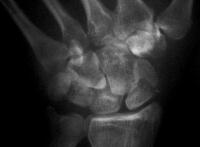

Case 5. Another,same bidirectional technique. Here, I ran the second screw too close to the first, and may have flattened the leading threads - not

ideal. The preop status:

Click for larger image